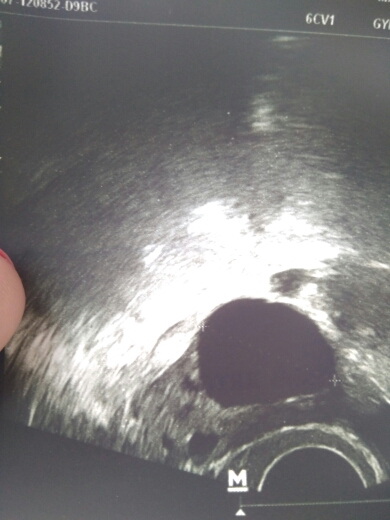

.Сегодня была на УЗИ. фол. 28мм, похоже перерос в кисту, но есть жидкость 10мм.там где и фол. 3 дня назад была на УЗИ фол. был 21, сделала укол ХГЧ 5000.Может он все-таки с овулировал? Или это киста надорвалась?Есть ли у меня шансы с такими показателями надеяться на овуляцию

?

На фото фоллик и рядом пятно это жидкость. Поделитесь положительным опытом.